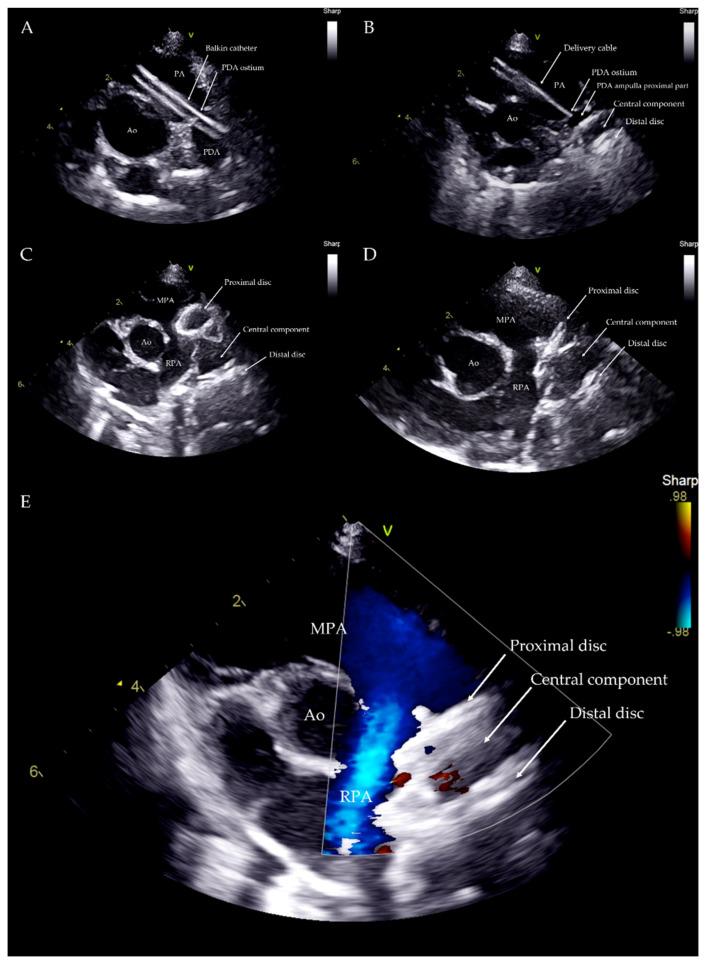

Although vascular plugs for the closure of patent ductus arteriosus (PDA) have been validated in dogs, studies are lacking on its use as a first-choice device with a transjugular approach. The present case series describes the transvenous right jugular embolization of PDA using an Amplatzer Vascular Plug II in seven dogs of different ages, breeds, and body weights. Complete closure of the PDA was demonstrated in all cases. All dogs showed significant hemodynamic reduction of pulmonary overcirculation and left heart size after the procedure and at following echocardiographic check-ups. Transjugular PDA occlusion using an Amplatzer Vascular Plug II can thus be considered as a safe alternative to the arterial or venous femoral approach using an Amplatzer canine ductal occluder (ACDO), particularly in puppies with small femoral vessels.

尽管用于闭合动脉导管未闭(PDA)的血管封堵器已在犬类中得到验证,但缺乏关于将其作为经颈静脉途径的首选装置的研究。本病例系列描述了使用Amplatzer血管封堵器II对7只不同年龄、品种和体重的犬经静脉右颈静脉进行PDA栓塞。所有病例均显示PDA完全闭合。所有犬在术后及随后的超声心动图检查中均显示肺循环过度和左心大小显著降低。因此,使用Amplatzer血管封堵器II经颈静脉封堵PDA可被视为使用Amplatzer犬用导管封堵器(ACDO)经动脉或股静脉途径的安全替代方法,特别是对于股血管较小的幼犬。